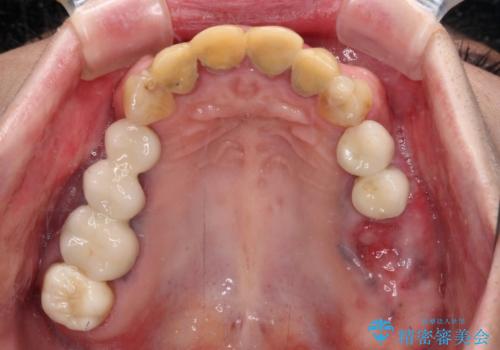

- 仮歯装着後に放置してしまい、恥ずかしいとのことで来院された患者様です。

仮歯が不適合で歯肉が腫脹していたため、しっかりと調整した新しい仮歯にして腫れを改善した上で、オールセラミッククラウンにて補綴することとしました。

日頃の歯磨きをしっかりと行ってくださるので、新しい仮歯に変えてから速やかに歯肉の状態が改善されました。

歯肉からの出血がほとんどないため精度の良い型取りができ、非常に適合の良い補綴治療を行うことができました。